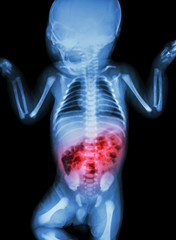

While appendiceal cancers are rare, tumors found in the appendix are often evaluated through an examination and biopsy. Since malignant appendix tumors can appear as ovarian or gastrointestinal cancers, they can be difficult to diagnose. The most prevalent tumors are carcinoid and measure fewer than two centimeters in size. Patients with this condition may not experience symptoms until the disorder has impacted the liver. Most appendiceal tumors are uncovered during screenings for other conditions.

Non-carcinoid tumors are more aggressive and can cause a buildup in biological substances that can lead to digestive problems. Tumors that have the ability to spread to the lymph nodes and other organs as well as very large masses are usually removed. Small, benign tumors may be monitored.